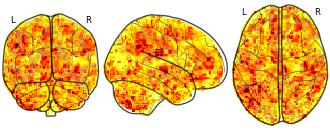

Anxiety involves anticipating aversive outcomes and can impair neurocognitive processes,

such as the ability to recall faces encoded during the anxious state. It is important to delineate

and determine the replicability of these effects using induced anxiety in the general

population, to understand its manifestation in anxiety disorders. This study therefore aimed to

replicate prior research on the distinct impacts of threat-of-shock-induced anxiety on the

encoding and recognition stage of emotional face processing, in a large asymptomatic sample

(n=92). We successfully replicated previous results demonstrating impaired recognition of

faces encoded under threat-of-shock. This was supported by a meta- and mega-analysis

across three independent studies using the same paradigm (n=211). Underlying this, a whole brain fMRI analysis revealed enhanced activation in the posterior cingulate cortex (PCC),

alongside previously seen activity in the anterior cingulate cortex (ACC) when combined in a

mega-analysis with the fMRI findings we aimed to replicate. We further found replications of

hippocampus activation when the retrieval and encoding states were congruent. Our results

support the notion that anxiety disrupts face recognition, potentially due to attentional

demands of anxious arousal competing with affective stimuli processing during encoding and

suggest that regions of the cingulate cortex play pivotal roles in this.Subject species

Anxiety involves anticipating aversive outcomes and can impair neurocognitive processes,

such as the ability to recall faces encoded during the anxious state. It is important to delineate

and determine the replicability of these effects using induced anxiety in the general

population, to understand its manifestation in anxiety disorders. This study therefore aimed to

replicate prior research on the distinct impacts of threat-of-shock-induced anxiety on the

encoding and recognition stage of emotional face processing, in a large asymptomatic sample

(n=92). We successfully replicated previous results demonstrating impaired recognition of

faces encoded under threat-of-shock. This was supported by a meta- and mega-analysis

across three independent studies using the same paradigm (n=211). Underlying this, a whole brain fMRI analysis revealed enhanced activation in the posterior cingulate cortex (PCC),

alongside previously seen activity in the anterior cingulate cortex (ACC) when combined in a

mega-analysis with the fMRI findings we aimed to replicate. We further found replications of

hippocampus activation when the retrieval and encoding states were congruent. Our results

support the notion that anxiety disrupts face recognition, potentially due to attentional

demands of anxious arousal competing with affective stimuli processing during encoding and

suggest that regions of the cingulate cortex play pivotal roles in this.Subject species